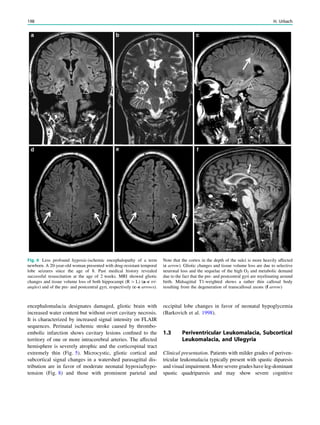

Fig. 1 Digital photogram of the brain surface before placement of a

Fig. 2 Epileptogenic lesion and symptomatogenic zone. A 40-year-

(a, arrow). Simultaneous video and EEG recordings from interhemi-

Clinical symptoms start around 1 s afterwards (d, asterisk)